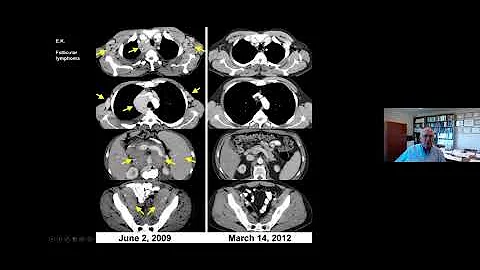

"The Development of Cellular Immunotherapy for Patients with Cancer," presented by Steven A. Rosenberg, MD, PhD.